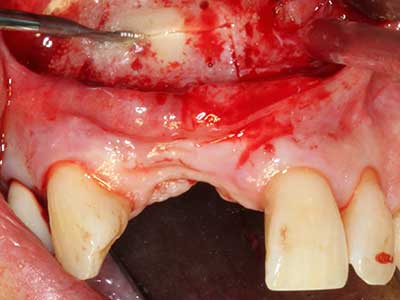

En la extracción de bloques óseos la piezocirugía también presenta ventajas adicionales: Además de la alta precisión en la osteotomía que ya se ha descrito antes, se ha comprobado que el uso de los delgados insertos de sierra resulta especialmente cuidadosas con el hueso. Frente a esto, sobre todo cuando se usan las fresas de Lindemann, cabe esperar pérdidas en la extracción significativamente más altas debido al mayor grosor de la parte frontal del cabezal (Lakshmiganthan, Gokulanathan et al. 2012). La separación basal que se necesita en particular en los injertos de bloque extraídos de forma retromolar se ve facilitada mediante sierras perpendiculares especialmente previstas a tal fin, lo que permite considerar que la cirugía piezoeléctrica es un procedimiento preciso y seguro para la obtención de bloques de hueso en el área retromolar (Happe 2007) (fig. 1-12).

El tejido óseo no solo tiene un contenido puramente mineral, sino que también presenta una importante proporción de fibras de colágeno. Esto no solo garantiza una buena resistencia a la presión, sino también una cierta flexibilidad, que puede aprovecharse para la realización de aumentos. En la plastia de expansión clásica a efectos de una partición ósea, la cresta maxilar atrofiada se divide en su eje longitudinal y, tras alcanzar una profundidad de osteotomía suficiente, se extiende con cuidado (fig. 13-16), en un caso ideal sin desperiostizar de forma visible el maxilar (Brugnami, Caiazzo et al. 2014, Stricker, Fleiner et al. 2014). Los sistemas de tornillos y placas con distancia de expansión creciente han demostrado su eficacia para distanciar entre sí las dos tablas óseas por debajo del umbral de rotura. Por regla general, se requieren anchuras de hueso residual de al menos 3 a 4 mm (Chiapasco, Zaniboni et al. 2006) para garantizar una flexibilidad y una cobertura ósea suficientes de los implantes que van a incorporarse. En caso necesario, una osteotomía de descarga vertical unilateral o bilateral puede mejorar la flexibilidad. Como alternativa a la técnica clásica se ha descrito una combinación con otras técnicas de aumento, sobre todo en la parte bucal.

Con el uso de sierras piezoeléctricas la división se efectúa de forma especialmente cuidadosa y sin pérdidas importantes de las dimensiones, por lo que no se han encontrado diferencias significativas entre los implantes realizados en el maxilar dividido y en la cresta alveolar no deficitaria (Chiapasco, Zaniboni et al. 2006, Danza, Guidi et al. 2009). No obstante, precisamente en la partición profunda y limitada de forma local, es preciso asegurarse de que exista una adecuada irrigación por agua para evitar que se produzcan sobrecargas térmicas en las áreas de osteotomía apical.